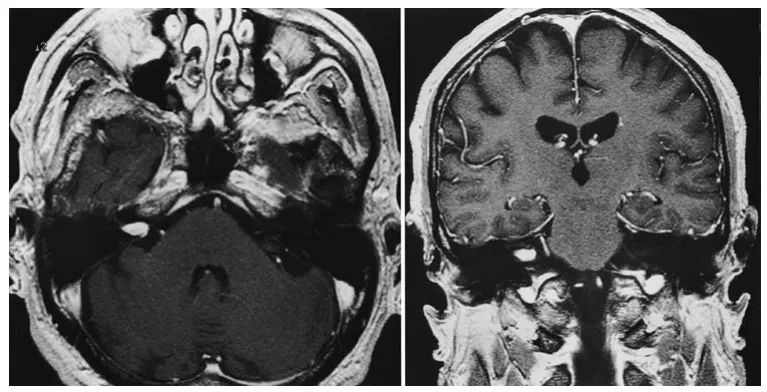

体格检查显示患者只能通过书写进行沟通;双耳听力完全消失,鼓膜检查正常。Romberg试验显示轻微摇晃。面部感觉和运动功能保持正常。急诊增强及平扫磁共振成像显示右侧内听道内有一个直径为1厘米的肿瘤,向右侧桥小脑角池区延伸约3毫米。